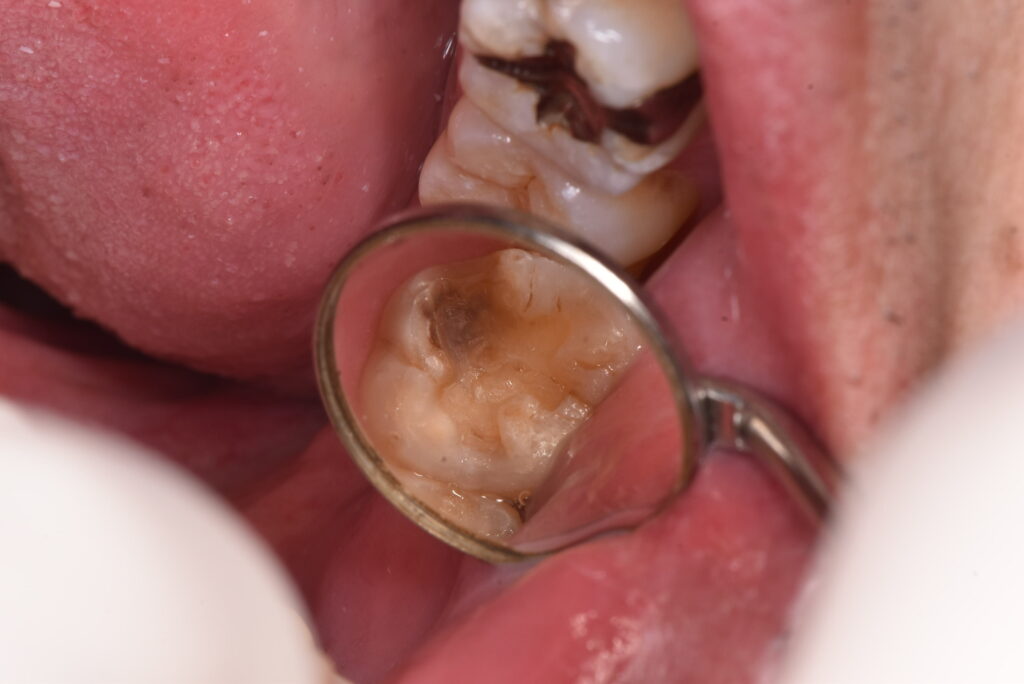

例を挙げます。下の写真をご覧ください。

治療されたものが取れて、処置となったケースです。一部だけ黒いのがわかるでしょうか?

削ってみると、かなり深いのがわかります。また、隣の歯との間に虫歯が隠れているのがわかると思います。